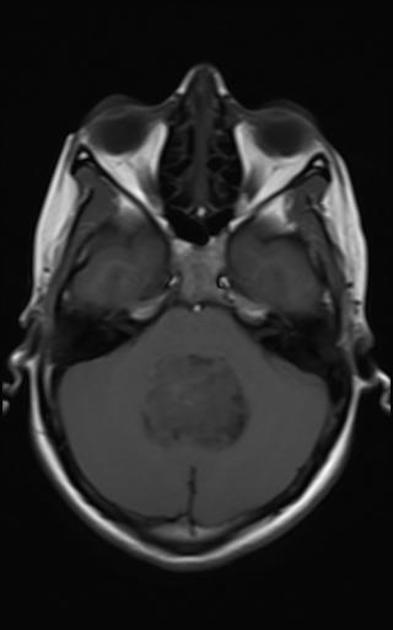

Axial T2Sagital FLAIR

Axial T1Axial T1 GadAxial T1 Gad/fat sat

For a detailed discussion of ependymoma imaging see Radiopedia for an excellent discussion on ependymoma imaging by Weerikoddy and Galliard.

MRI Brain

Careful examination of the entire neuraxis is required to assess for the presence of CSF seeding.